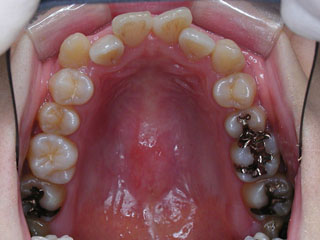

主訴:上顎前歯の突出 口が閉じにくい

診断名:叢生と伴う上顎前突

年齢:13歳

使用した主な装置名:TPB、HG、マルチブラケット装置

抜歯/非抜歯および抜歯部位:抜歯(上顎左右第一小臼歯)

治療期間:動的処置2年6か月、経過観察3年6ヶ月

上顎前歯の前突が見られます。下の歯には中程度の叢生と口唇前突感がみられました。分析結果では、2級1類と呼ばれるタイプの不正咬合でした。上顎の左右第一小臼歯を抜歯してマルチブラケット治療を行いました。